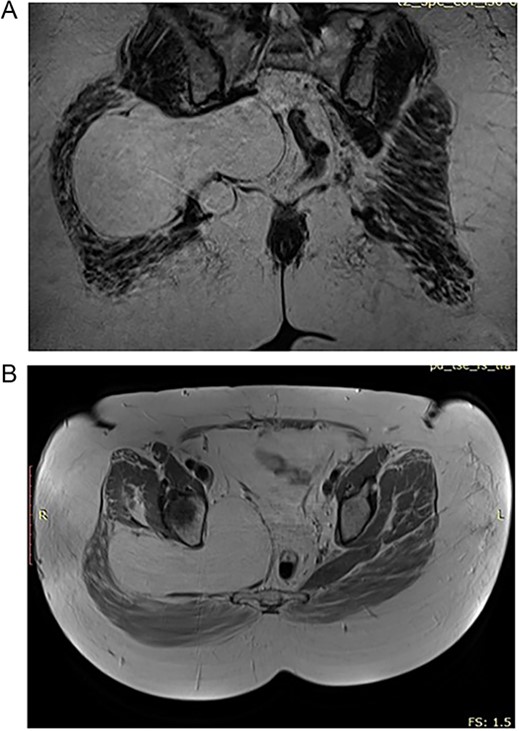

In the 55-year-old female, consequently were done a CT scan and MRI imaging (Fig. 2A and B). The patient had a different surgical history compared to the other female representative. She was operated in another medical unit due to spinal stenosis and nerve root decompression following spinal stabilization was performed. However, the complaints were persistent and on a second MRI, the team of neurosurgeons, who performed the operations on both of the presented cases, noticed a mass corresponding with the characteristics of lipoma and being the predominant reason for the complaints as it caused sciatic pain.

(A) Preoperative CT of the 55 year old patient with lipoma in the pelvic region. (B) Preoperative CT of the 55 year old patient with lipoma in the pelvic region.